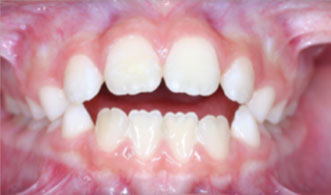

Thumb sucking is a very normal process for babies and toddlers. It is soothing and calming, and there is no reason to worry if your child is under 5 years of age. In most cases, if the thumb habit is ceased around age 4-5, the permanent teeth will come in (around age 6) just fine. However, if the habit persists beyond the time the permanent teeth begin to erupt (age 6), the bite becomes affected. As a child sucks his or her thumb, a tremendous negative pressure is created inside the mouth, while outside, the cheeks are

being contracted at the same time. The characteristic bite of thumb sucking is “protruding” or flared upper front

teeth, spacing between the upper front teeth, open bite (see picture

below-where front teeth don’t touch), and a narrowed upper jaw (due to the

negative pressure inside the mouth and the positive pressure from the cheeks “pushing”

on the back. These characteristics can

do many things to affect the eruption of the other permanent teeth. For example, too narrow of a palate means

insufficient space to accommodate all the remaining permanent teeth. Also, the pressures created can also impact

the formation of the jaws, where the lower jaw remains much further back than

the upper jaw.